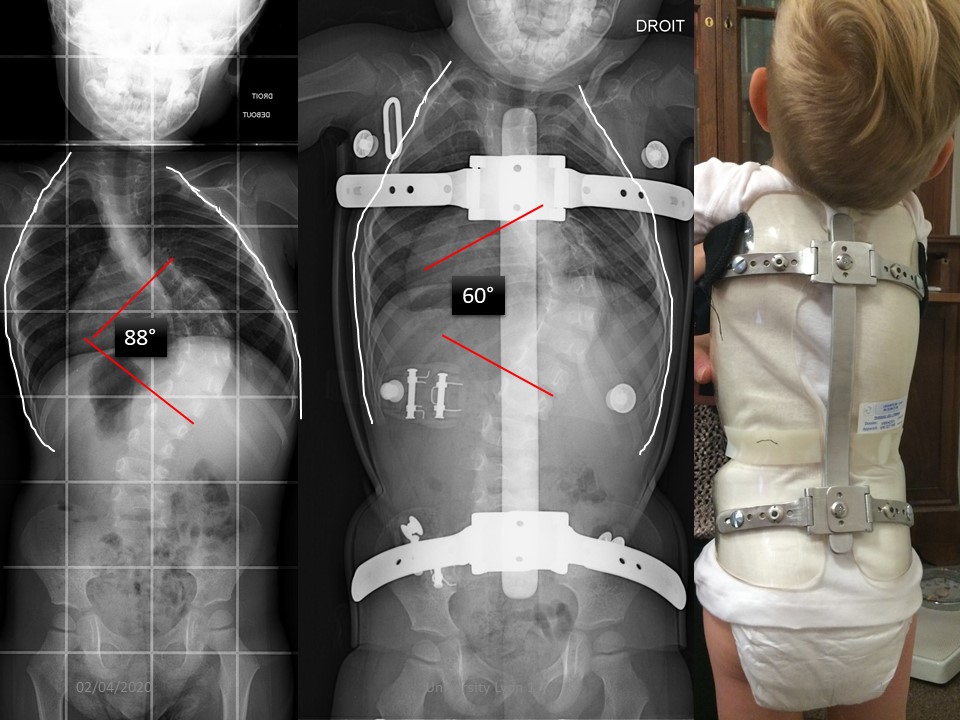

Sometimes after the serial casting, it is often too early to consider surgery. In this child a corset Chêneau has been made. |

|

But the Chêneau brace realized did not maintain the high thoracic curvature and especially was not tolerated by the child |

Mom wishing to try the new Lyon ARTbrace, a mirror CAD/CAM is done. The child is stretched to the maximum while standing. Only one scan is done and the positive is achieved by reversing right and left. |

The comparison with the Chêneau is favorable with better maintenance of the thoracic cage at the upper part and improvement of the angular correction. |

In the sagittal plane, the balance is also better. |

Clinical aspect in ARTbrace with polycarbonate of 3 mm. The day after the fitting the child goes tobogganing. At the last control the angulation was stable at 58 ° without brace. A large anterior thoracic expansion is performed to complete the expansion of the concavity. |